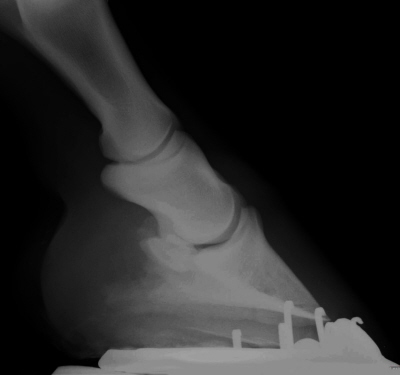

Seitliche Röntgenaufnahme abgesehen von Hufknorpelverknöcherung weitgehend unauffällig